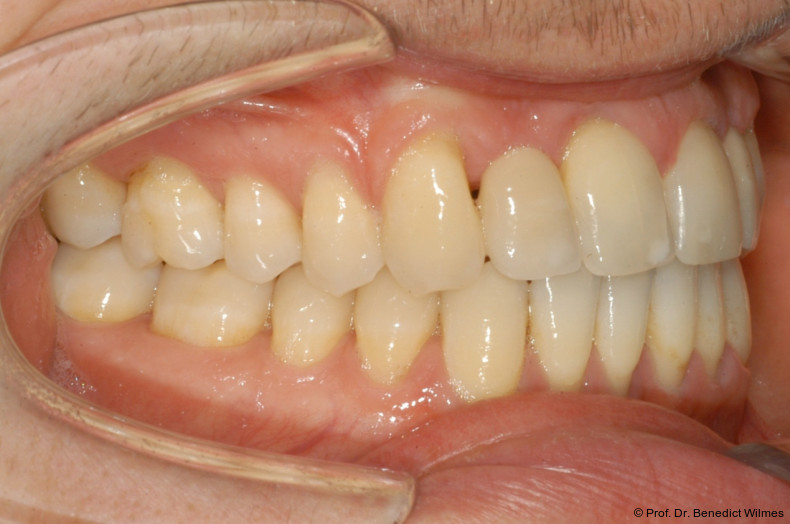

Ein 14-jähriger Patient wurde bei Aplasie der beiden oberen seitlichen Schneidezähne mit dem Ziel der beidseitigen Lückenöffnung kieferorthopädisch therapiert (Abb. 1a+b). Zum Ende der kieferorthopädischen Behandlung wurden zwei Miniimplantate in Regio 2er als temporärer Zahnersatz inseriert (Benefit System, PSM, 2 x 13 mm, Abb. 2a+b). Nach Abdrucknahme wurden Kronen auf den Peek-Abutments modelliert und diese mit Kunststoff auf die Abutments geklebt (Abb. 3a–d). In den Abbildungen 3 und 4 sind die klinischen und röntgenologischen Nachkontrollen innerhalb der nächsten achteinhalb Jahre dokumentiert. Man erkennt einen sowohl in der Höhe als auch in bukkopalatinalen Breite verbleibenden gesunden Knochen ohne Anzeichen einer Atrophie. Im Alter von 23 Jahren wurden die definitiven Implantate ohne die Notwendigkeit einer Augmentation eingesetzt (Abb. 5) und nach Einheilung prothetisch versorgt (Abb. 6a–e und Abb. 7a–c).